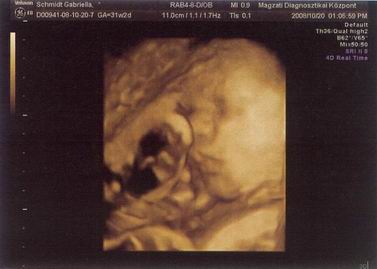

Kicsikristóf a 32. hét elején (vagyis épp egy hete).

BPD: 86 mm

HC: 313 mm

AC: 305 mm

FL: 61 mm

Becsült súly: 2280 gr :shock:

Számított terhesség: 31+2

Biometria alapján: 33+4

itt épp orrba rúgja magát :D

bucifej: